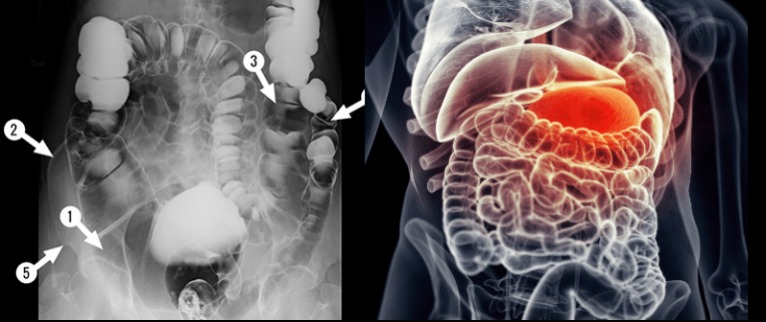

A szervezetbe kerülő toxinok egy része a bélrendszeren keresztül választódik ki. A hagyományos kínai orvoslás ezért hangsúlyozza gyakran, hogy számos betegség a belek működésével hozható összefüggésbe. Ha a bélrendszer nem működik megfelelően, a salakanyagok és káros anyagok könnyebben felhalmozódhatnak a szervezetben, ami hosszabb távon különféle panaszokat okozhat.

Normális körülmények között az elfogyasztott ételek lebontása és végighaladása az emésztőrendszeren körülbelül egy napot vesz igénybe. Ha azonban az étrend túl zsíros, rostszegény, vagy rendszertelenül étkezünk, az emésztési folyamat lelassulhat. Egyes esetekben a táplálék feldolgozása akár 48–72 órát is igénybe vehet, ami különböző kellemetlen tünetekhez vezethet.

Az egyik leggyakoribb figyelmeztető jel a székrekedés, amely arra utalhat, hogy az emésztőrendszer működése lelassult. Ilyenkor a szervezet nehezebben tud megszabadulni a felesleges anyagoktól.

Amikor a szervezetben túl sok salakanyag halmozódik fel, többféle jel is utalhat erre. Az immunrendszer gyengülése például gyakran megjelenik különböző bőrproblémák formájában: ekcéma, bőrkiütések, gombás fertőzések vagy gyakori vírusos és bakteriális megbetegedések is jelentkezhetnek.

A bélrendszer állapota a hangulatra is hatással lehet. A gyakori hangulatingadozás, memóriazavar, szorongás vagy tartós levertség mögött sokszor az emésztőrendszer egyensúlyának felborulása is állhat. Emellett előfordulhat általános izomgyengeség, valamint különféle emésztési panaszok, például hasi fájdalom, puffadás, hasmenés vagy székrekedés.

Ezért is fontos a kiegyensúlyozott, rostban gazdag étrend, a megfelelő folyadékbevitel és az egészséges életmód. Ha a bélrendszer megfelelően működik, az nemcsak az emésztést segíti, hanem az egész szervezet közérzetére és egészségi állapotára is kedvező hatással lehet.